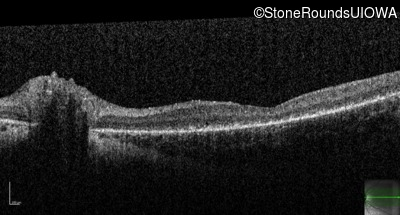

Age at visit: 10 years

Age at visit: 11 years

Age at visit: 13 years